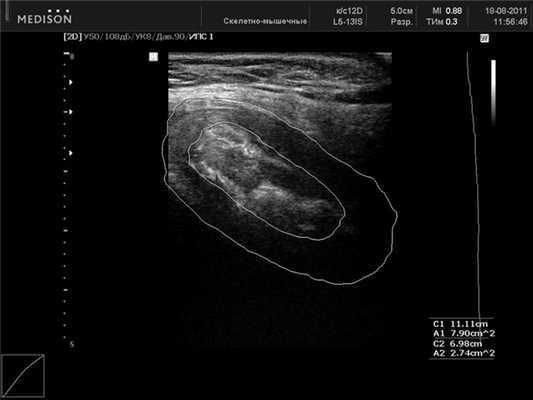

УЗИ ЛС проводили во фронтальной (рис. 3) Рисунок 3. Лонное сочленение. УЗ-сканирование во фронтальной проекции. и сагиттальной (рис. 4) Рисунок 4. Лонное сочленение без признаков дисфункции. УЗ-сканирование в сагиттальной проекции. проекциях при помощи трансабдоминального конвексного мультичастотного датчика с частотой 2-6 МГц или линейного датчика 5-12 МГц. Использование линейного датчика ограничено у тучных пациенток. Проводились измерения высоты, толщины симфиза и ширина его в верхней и нижней трети. Кроме того, мы исследовали площадь сечения межлобкового хрящевого диска (discus interpubicus), отношение этой величины к площади сечения всего сочленения, размер хрящевого пояса лобкового симфиза. Полученные результаты сравнивали с ранее полученными рентгенологическими и эхографическими данными. В качестве дополнительного метода исследования изучалась эхоплотность хрящевой межлобковой пластинки у женщин. Построение гистограмм плотности тканей ЛС у всех пациенток обследованных групп проводилось в одинаковых режимах сканирования. Гистограмма представляет собой тип диаграммы, отражающей распределение эхосигналов и позволяет сравнивать относительную плотность ткани по уровню градации «серой шкалы» в условных единицах. Учитывая максимальную зависимость получаемых значений эхоплотности от индивидуальных настроек аппарата, считали целесообразным использование не абсолютных показателей данного параметра, а относительных условных единиц. В основу математической обработки материала были положены непараметрические методы математической статистики с вычислением медианы интерквартильного размаха (значений 25-го и 75-го перцентилей) для каждого показателя. Сравнение групп наблюдения друг с другом производили с помощью ряда непараметрических критериев (Вилкоксона-Манна-Уитни, Смирнова, Фишера, χ 2 ).

Ультразвуковая структура лонного сочленения. При УЗИ в поперечном сечении в положении датчика на передней поверхности лона лобковый симфиз представляет собой неоднородное, средней эхогенности образование, расположенное между эхотенями лобковых костей. В центре симфиза визуализируется более эхоплотное «ядро» ЛС, неоднородное за счет чередования участков различной эхогенности. «Ядро» окружено более гипоэхогенным хрящевым ободком. Над ним визуализируется в большинстве случаев lig. pubicum superius. На данных ультразвуковых срезах возможно измерить ширину ЛС как по верхнему, так и по нижнему краю. Ориентиром служат лобковые кости.

При сагиттальном сканировании ЛС представляет собой овальное образование неоднородной структуры с четко выделяемым «ядром», включающим гипер- и гипоэхогенные участки. По наружной поверхности хрящевого пояса в большинстве случаев удается дифференцировать по верхнему краю lig. pubicum superius, снизу - lig. arcuatum pubis, спереди - lig. fibrosum anterior и сзади - lig. fibrosum posterior. Они служат ориентирами при измерении размеров лобкового симфиза. При сравнении ультразвуковой картины с данными проведенных ранее (М.Ф. Айзенберг, 1962) морфологических исследований можно предположить, что гипоэхогенный ободок симфиза является гиалиновой частью хрящевого диска, гиперэхогенное «ядро» - участки замещения фиброзным хрящом. В структуре хрящевого пояса могут обнаруживаться гиперэхогенные включения округлой или неправильной формы, являющиеся, вероятнее всего, зонами оссификации (см. рис. 4). Сагиттальные ультразвуковые срезы у края правой или левой лобковых костей представляют собой более или менее однородную овальную гипоэхогенную структуру ткани хрящевого диска с гиперэхогенным (дающим тень) краевым срезом лобковой кости. Линейные размеры ЛС у женщин при ультразвуковом исследовании представлены в табл. 1.